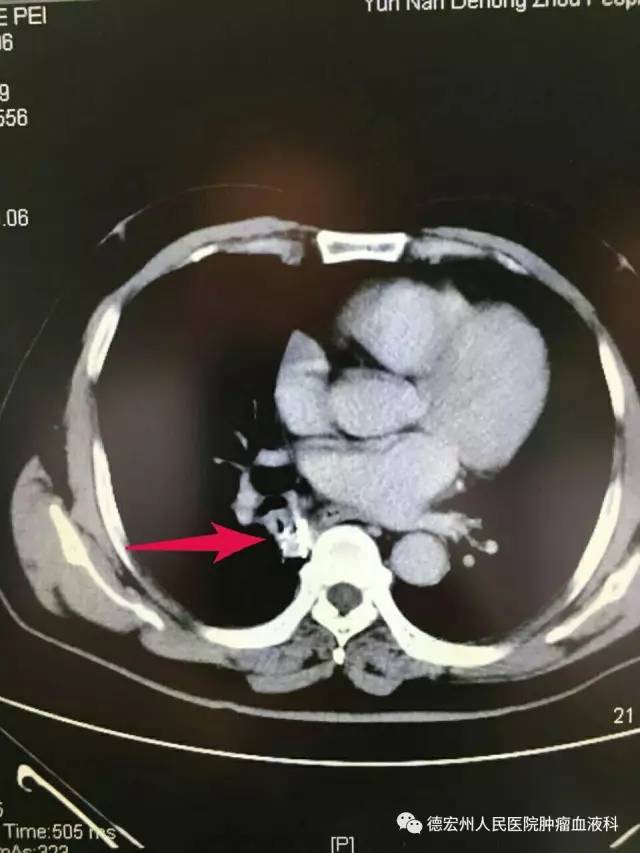

患者一,男,74岁,因乏力、纳差10余天于今年4月到州人民医院就诊,CT检查发现:患者右肺肿块。经CT引导下肺穿刺活检术,术后病理:右肺下叶鳞状细胞癌。患者确诊后转诊至省级医院,拟行外科手术治疗,但由于患者高龄,基础疾病较多(高血压、糖尿病、脑梗塞、肾功能不全等)不能耐受外科手术。于6月再次到州人民医院肿瘤血液科就诊,并于6月24日在CT引导下行经皮肺穿刺右下肺癌粒子植入手术治疗。 8月回院复诊时发现,其右下肺癌肿块消失。碘125粒子植入术又称体内伽玛刀,是肿瘤近距离放射治疗的一种,是治疗肿瘤的新手段。该项技术在局麻下完成,有创伤小、并发症少、术后恢复快等优点。从本患者的医治情况看,此技术疗效确切,获得满意的治疗效果。

② 术后右下肺肿块消失